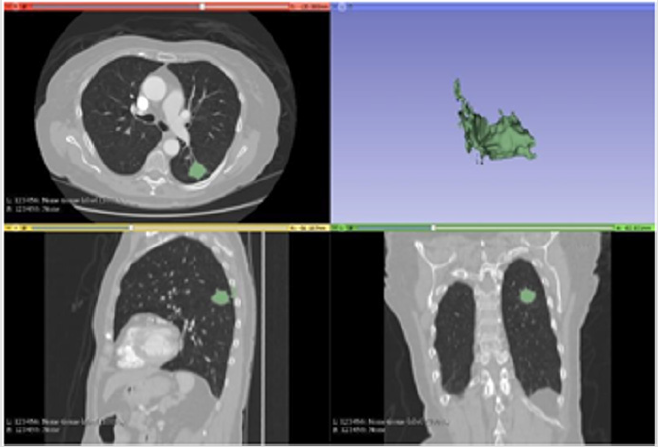

Figure 3: Segmentation with proposed method.

Note: The Figure 3 illustrates the result of the proposed algorithm. a particularity of this algorithm is given by the automation of the whole process, from the marking of the area of interest at the beginning all the remaining process until the 3D illustration is done automatically, in other hands the algorithm was also able to reduce the time for the execution of the segmentation task even more, staying in fast 2s.